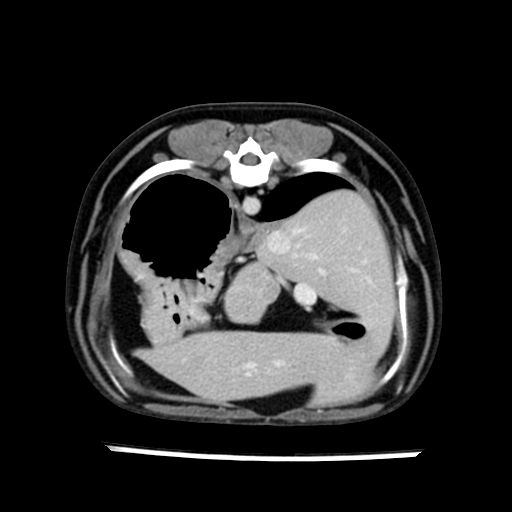

prescritto esame TAC

sequenza immagini limitata al fegato reni e surreni

le immagini ecografiche rispetto alla tac datano circa 7 mesi prima ,le surrenali sono normali nonostante il test acth sia risultato positivo .all’esame TAC dopo diversi mesi risultano aumentate armonicamente nel volume e si individua un forte sospetto di adenoma ipofisario .

sospetto adenoma ipofisario vs. meno probabilmente meningioma della base; intertiziopatia polmonare; lesione espansiva epatica, verosimilmente del lobo laterale sinistro, di sospetta natura neoplastica; lesioni spleniche di natura da definire; iperplasia/ipertrofia delle ghiandole surrenali, bilateralmente; vertebra di transizione del rachide toracico; tenosinovite cronica del muscolo bicipite brachiale di destra.